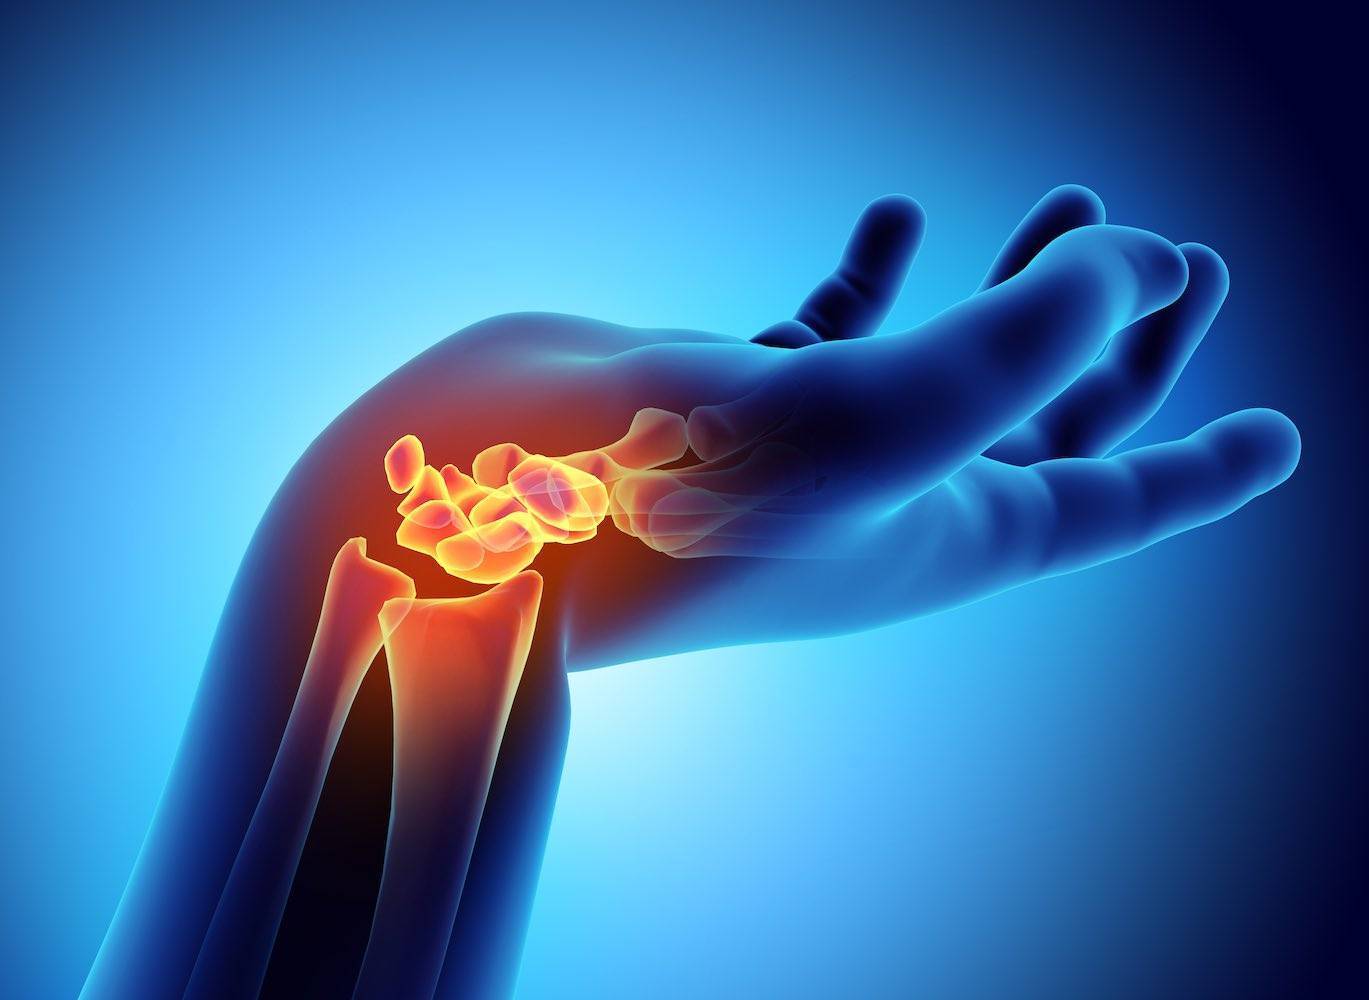

Die Orthopädie ist ein medizinisches Fachgebiet, das sich mit der Prävention, Diagnose und Behandlung von Erkrankungen und Verletzungen des Bewegungsapparates beschäftigt. Knochen, Gelenke, Muskeln, Sehnen und Bänder müssen gemeinsam funktionieren, um uns Beweglichkeit und Stabilität zu ermöglichen.

Auf unserer Seite finden Sie umfangreiche Informationen zu orthopädischen Beschwerden und Erkrankungen. Von der Arthrose über Bandscheibenvorfälle bis hin zu Kreuzbandriss und weiteren Sportverletzungen: wir geben Ihnen einen Überblick über die häufigsten orthopädischen Krankheitsbilder, wie sie behandelt werden können und inwieweit ein Bildgebungsverfahren, wie eine (z.B. MRT Knie, Rücken MRT) bei der Diagnose bei der Diagnose unterstützend wirken können.

Unsere Liste zu den häufigsten orthopädischen Problemen ist alphabetisch von A-Z geordnet. So finden Sie schnell und unkompliziert den Beitrag, der Ihnen weiterhilft. Von Krankheiten, über Verletzungen bis hin zu schmerzhaften Zuständen wie Arthrose, Meniskusschaden und Schleimbeutelentzündung – hier finden Sie die wichtigsten Informationen.